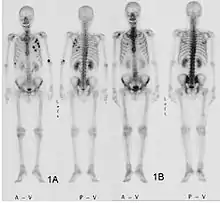

Fracture pathologique du bras gauche sur une métastase osseuse de cancer du sein

Scintigraphie corps entier avec 99mTc-HDP de la patiente avec une fracture du bras due à une métastase du cancer du sein